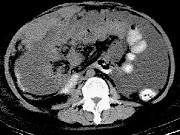

问题 男,51岁,直肠癌术后1年,腹胀,纳差,消瘦,影像检查如图,最可能的诊断是()

选项 A.直肠癌肝转移 B.直肠癌网膜转移 C.肝硬化腹水 D.术后改变 E.肠梗阻

答案 B